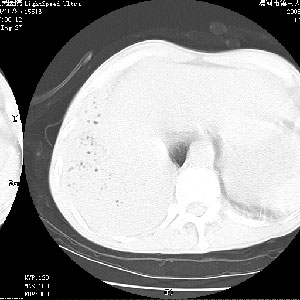

m 老年 发烧、呼吸困难,慢支、肺气肿多年;记的那次是下午大概17:38做的,晚上窒息死亡。

上面的层面就慢性支气管炎肺气肿、肺大泡,别的没有什么、也就不传了。

当时我怀疑:1、阻塞性肺不张早期 2、肺脓肿早期,望老师们发表意见

应该是脓胸的表现,右下肺气管阻塞考虑为痰栓.

你怀疑的有道理,慢支、肺气肿、肺打泡是有了,右下肺的病变有待商议;

首先考虑右下肺炎症并不张,不除外早期肺泡癌改变

病灶边缘清---多个含气小腔---近端未见通畅气管影-----支持-----慢性肺脓肿继发阻塞性肺不张

阻塞性肺不张原因-----脓液未排出

1、右侧脓胸;2、copd;

3、细支气管肺泡癌可以排除,病变以斜裂为界,呈大片状高密度影,内可见多发小气泡,表明有产气杆菌感染所致,内无明显的支气管“枯树枝征”表现,再结合其临床改变(细支气管肺泡癌临表表现重、影像表现轻)所以不符合细支气管肺泡癌(炎症型)的改变。

病变按肺叶分布,病变内可见多个小空腔影,未见充气支气管影,中间段支气管管腔肺窗示密度欠均匀,下肺支气管分叉处基底段支气管隐约可见,未见明显狭窄,中叶支气管通畅,

考虑:阻塞性肺炎伴小脓肿形成可能性大。(痰栓可能性大)

右下肺实变,内有弥漫分面小气泡而无支气管征,叶间裂前移,呈臌大之形,而无收缩之状,兼纵隔稍左行移,故。不支持不张,倒支持大叶肺叶,如楼上所说,小气泡不象残留之肺,不可以考虑产气菌感染吗。

阻塞性肺炎,肺脓肿形成。依据,右下支气管不通,大片实变形内可见小气泡。不支持肺不张。